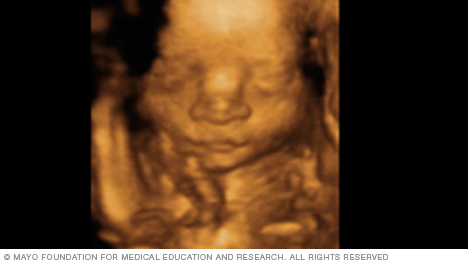

The image below is from a 3D fetal ultrasound. This type of ultrasound can make images that are clearer and more detailed than standard fetal ultrasound images. A 3D fetal ultrasound is sometimes used to detect facial problems, bone problems or neural tube defects.

Some companies offer 3D ultrasounds outside of medical settings. These ultrasounds are often advertised as a way for families to create keepsake images or to learn the sex of a fetus. But most health care professionals advise against getting fetal ultrasounds, including 3D ultrasounds, when there's not a medical need for them.